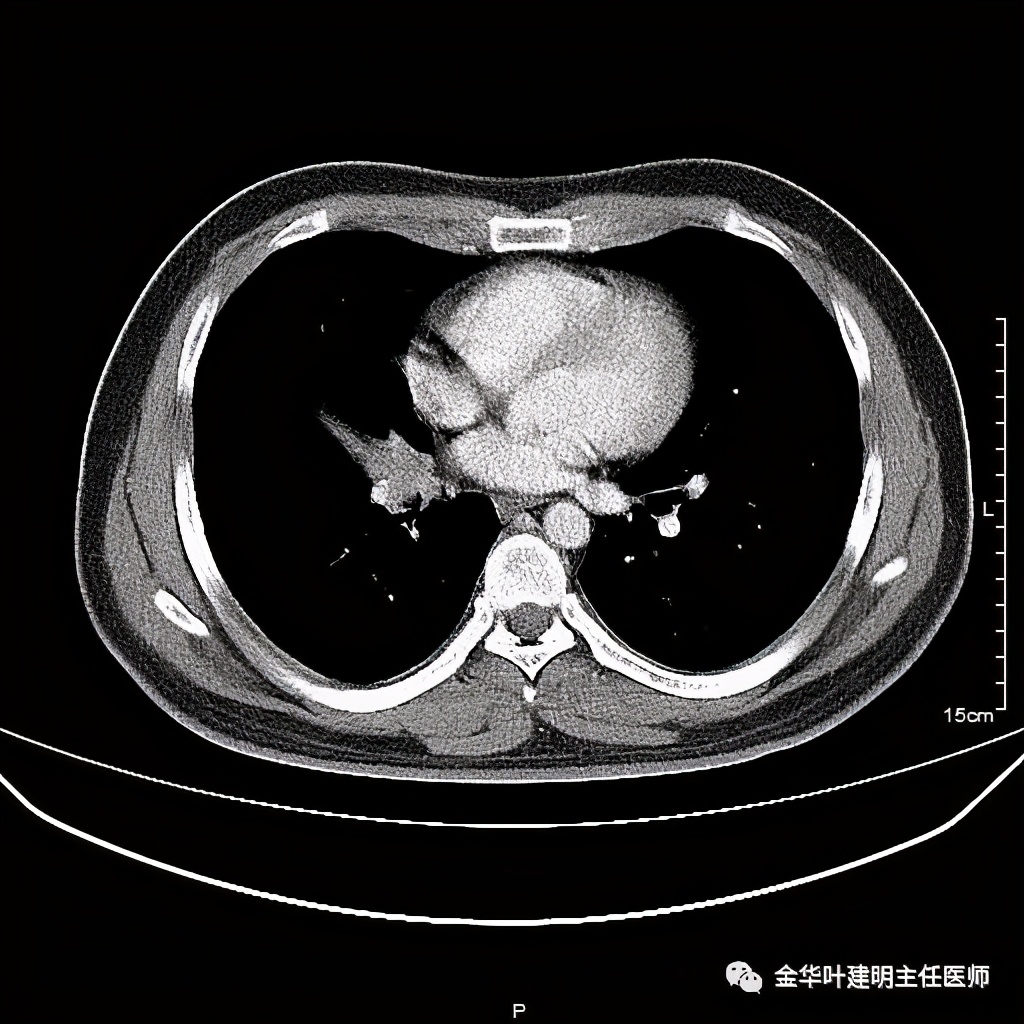

七、浸润性腺癌的其他型:

上图病例为实性,病理上实体型占80%,腺泡型占20%

上图此例也是实性结节,病理报告:实体型伴神经内分泌;

上图此例的实性肿块,病理是:微乳头为主,部分实体型,当时没注明占比;

上图此例实性结节,是实体型,我们发现其影像特征: 病灶有浅分叶、细毛刺、支气管截断征、膨胀性,密度高而密 (比腺泡型实、比粘液癌高、比鳞癌或小细胞癌更具膨胀性)。

但是上面这几例,因为不管怎样的组合,都是实性密度+实性密度,这时仅从影像上就非常难以判断具体的亚型,不过,我们要根据相关的影像特征判断它为恶性,而且该尽早取得病理依据,能手术的要抓紧、不能手术的也要穿刺等得到病理类型的确诊后积极治疗,这就够了!